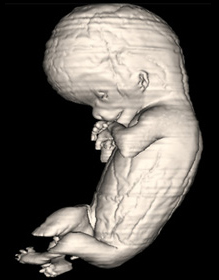

Carnegie Embryo #9226 | Location: 138-01-01

Source: The Virtual Human Embryo.